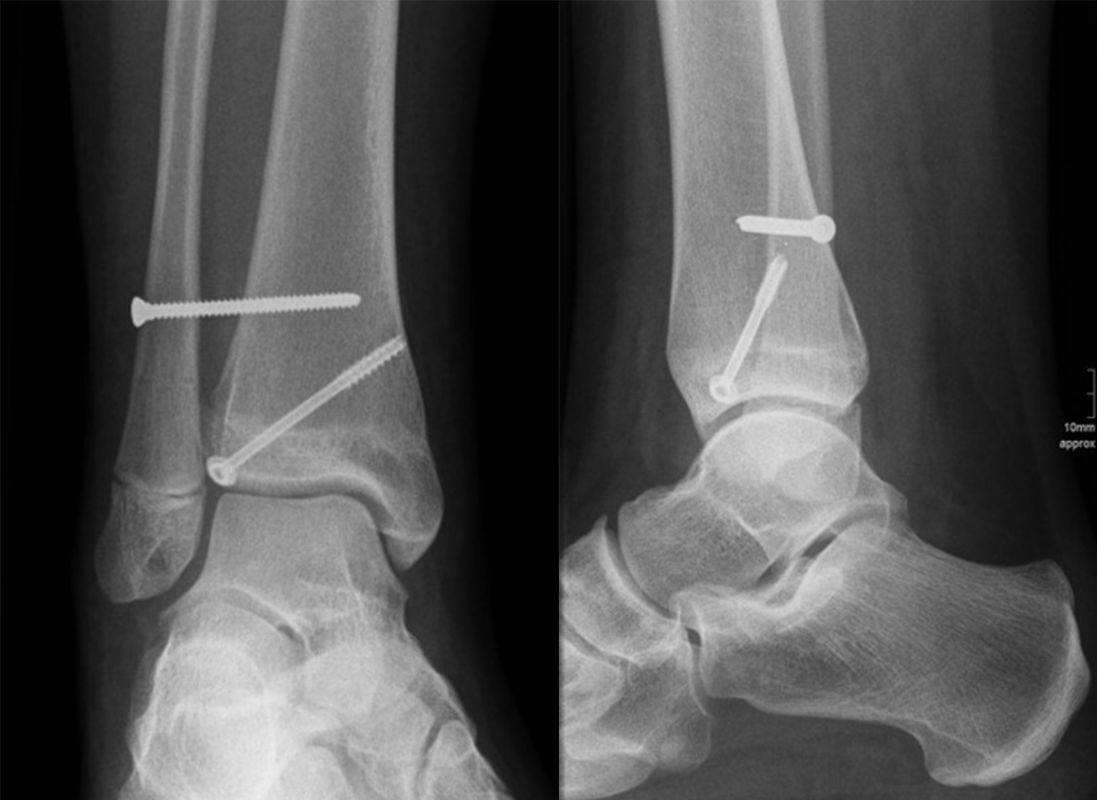

Behandlungsziel ist die exakte Rekonstruktion der Gelenkfläche sowie die Minimierung des Risikos einer späteren Wachstumsstörung. Dislozierte Frakturen werden offen reponiert, die Osteosynthese erfolgt mit einer Kleinfragmentschraube. Finden sich viele kleine Fragmente kann eine K-Draht Osteosynthese durchgeführt werden. Wird der Innenknöchel operiert, kann bei gleichzeitiger hochgradiger lateraler Instabilität eine Rekonstruktion des lateralen Bandapparats durchgeführt werden. Fibula Frakturen stellen sich meist spontan ein, sodass hier keine zusätzliche Osteosynthese notwendig ist.

Nach der Osteosynthese wird die Fraktur für ca. vier Wochen in einem Unterschenkelgips ruhiggestellt. Bei Schmerzfreiheit der Frakturzone erfolgt anschließend eine schmerzadaptierte Belastungssteigerung über weitere zwei Wochen. Sobald unter Alltagsbedingungen Beschwerdefreiheit besteht kann die sportliche Belastung langsam gesteigert werden. Kirschnerdrähte werden 6-8 Wochen postoperativ, Schrauben nach zwölf Wochen entfernt. Es empfiehlt sich klinische und radiologische Kontrollen im Abstand von 6 Monaten bis zum Wachstumsabschluss durchzuführen, um ein mögliches Fehlwachstum frühzeitig zu erkennen.

Dislozierte Frakturen (Frakturspalt > 2 mm) werden grundsätzlich operativ behandelt. Die Reposition kann arthroskopisch unterstützt erfolgen. Die Schraubenosteosynthese erfolgt entsprechend dem Frakturverlauf. Bei Twoplain Frakturen ist meist eine epiphysäre Schraube ausreichend die von lateral kommend das Fragment nach medial-proximal fixiert. Der Schraubenverlauf ist üblicherweise von lateral ventral nach proximal dorsal medial (Abb. 24). Nach Reposition darf in der seitlichen Aufnahme des Sprunggelenks, als auch in der 45° Außenrotationsaufnahme keine Stufe in Höhe der Wachstumsfuge erkennbar sein. Eine sichtbare Stufe ist Indikator für eine unzureichende Reposition.

Bei Triplane-Frakturen fasst die metaphysäre Schraube das metaphysäre Fragment einschließlich eines hinteren Volkmann Dreiecks, die epiphysäre Schraube fasst das epiphysäre Fragment. Da der Fugenschluss noch nicht abgeschlossen ist, sollten die Schrauben die Wachstumsfuge nicht kreuzen, obwohl eine Wachstumsstörung unwahrscheinlich ist (v. Laer 2013).